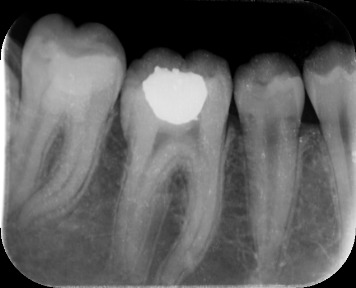

Methods: A 16 year old girl presented with bilateral carious mandibular second molars. She had symptoms of irreversible pulpitis in both the teeth. Parents refused extractuions and were reluctant to proceed with root canal therapy. After informed consent Biodentine Pulpotomy was attempted on both teeth followed by permanent composite resin restorations.

Results: The patient became asymptomatic in both teeth after the procedure. Vital radicular pulp was preserved and root canal treatment avoided